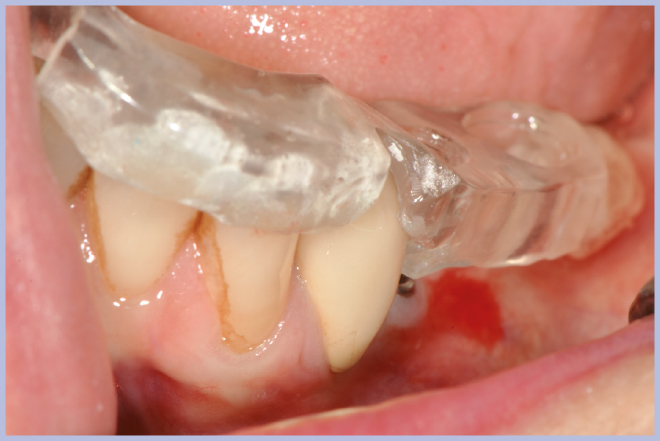

- Figg. 31-35 – Al momento della riapertura utilizzo della guida chirurgica per l’esposizione implantare

- Fig. 32